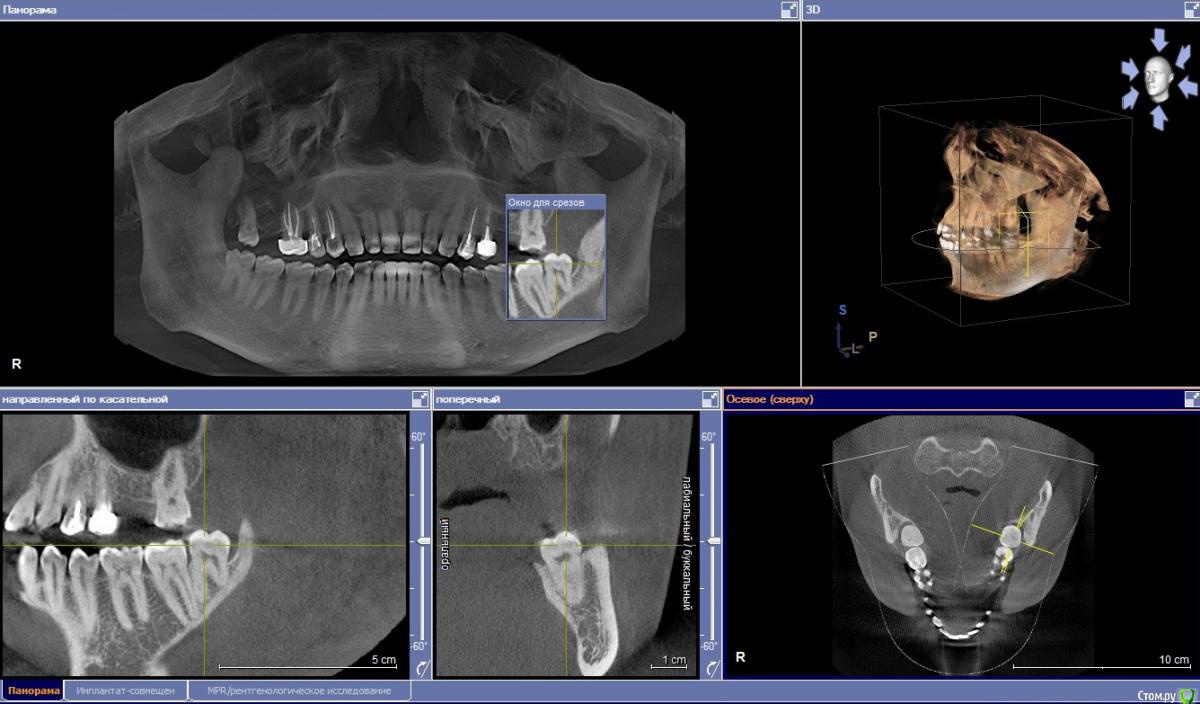

posman Опубликовано 8 октября, 2018 Поделиться Опубликовано 8 октября, 2018 (изменено) Здравствуйте! Просьба проконсультировать касаемо возможной "природы" образований на фото.Наросты выявлены около 10 лет назад при очередном осмотре у ЛОР-врача.Симметричны с двух сторон языка, на левой стороне более выражены. Динамика роста отсутствует, в последние 2 месяца отмечена некоторая болезненностьс левой стороны у корня языка, отдающая в область нижнего 8го зуба и небной дужки(ноющий дискомфорт в т.ч. при употреблении пищи). В ночное время боль отсутствует. За последнюю неделю слева появилось небольшое желтое "включение", м.б. нагноение (видно на фото в динамике). В течении двух месяцев посетил трех лоров, чл-хирурга и двух специалистов по слизистым,выполнено МРТ мягких тканей шеи (без патологий).Фарингоскопия также патологий не выявила, ЧЛХ связал болезненность с 8м зубом, который до конца не прорезалсяи имеет десневой карман. Один специалист по слизистым поставил глоссит, второй коллега указал на вероятную глоссалгию.Касаемо "наростов", мнение стоматологов - физиология и сосочки языка. ЛОРы - лимфоидная ткань язычной миндалины.За время "истории" прошёл противогрибковую терапию (флюкостат), антибиотики не употреблял. бак-посев не выявил патогенной микрофлоры, ОАК месячной давности в пределах нормы. По сути, интересует три момента:1. Природа наростов. Понимаю, что точно может показать только гистология, но хотя бы визуально. 2. Возможная связь дискомфорта с зубом мудрости, карманом или др.неврологической причиной. 3. "Гнойник" на наросте, что делать, как лечить. Фото языка и 8ки, а также снимок ОПТГ прилагаю. Буду признателен за комментарии. Изменено 8 октября, 2018 пользователем posman Ссылка на комментарий

posman Опубликовано 9 октября, 2018 Автор Поделиться Опубликовано 9 октября, 2018 и... забить 10 лет так и делал, пока не возник дискомфорт в этой области. Еще вопрос: что можно сказать по 8ке исходя из снимка ОПТГ? Мнение двух стоматологов разошлись: 1. зуб без кариеса и пока удалять не стоит. Предлагают устранить карман сбоку. Стоит это делать?2. 8ке не хватает места и она давит на рядом стоящий 7й зуб, что может привести к кариесу и потере последнего, т.е. необходимо удаление зуба мудрости. Также уточните пожалуйста, пока не попаду к врачу, стоит ли чем-то обрабатывать воспаление (желтый гнойник сбоку).Появился за пару дней. м.б. пополоскать содой? или по фото совсем не понятно что это? Ссылка на комментарий